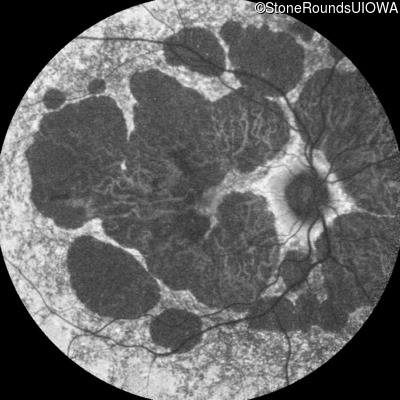

AR Stargardt Disease (IIA)

Case Level Images